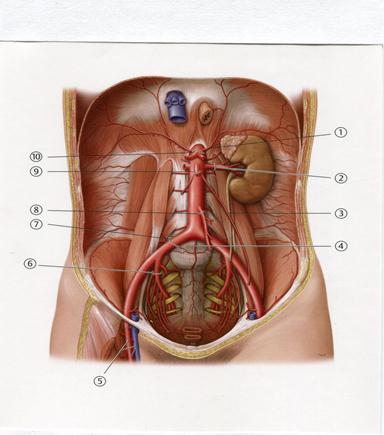

С. Жоғарғы қуыс

+A. Бүйрек венасы

C. Құрсақ сабауы

D+++++. Төменгі шажырқай артериясы

E. Ішкі мықын артериясы